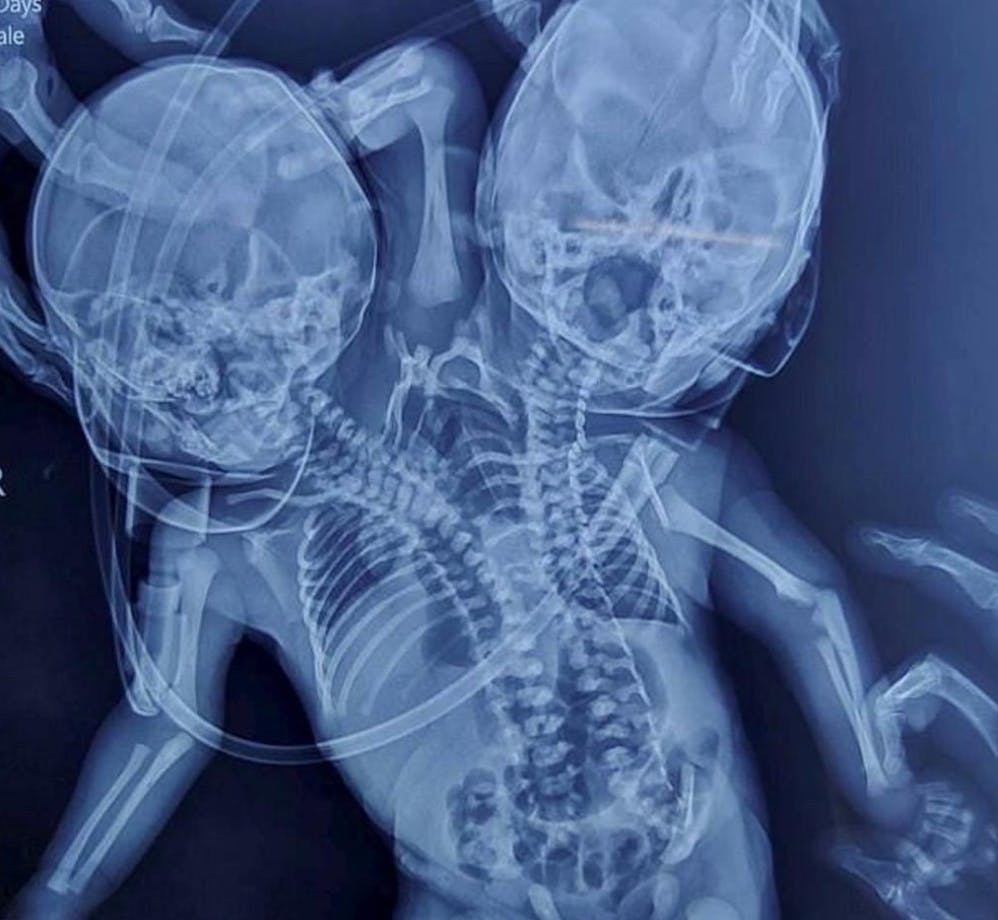

For i stedet at give fødsel til to raske babyer, fødte Shaheen Khan et barn med to hoveder, tre hænder og to hjerter.

Hvor siamesiske tvillinger, som nok kommer tættest på, er to kroppe, som sidder sammen ved fødslen, så er der i dette tilfælde altså kun en torso, hvilket blandt andet er grunden til den manglende operation.

Den helt nøjagtige betegnelse for de to er dicephalus parapagus. Dicephalis betyder tohovedet, og parapagus betyder side om side.

Alligevel kan det virker lidt spøjst, at den tredje arm, der kommer bagfra og går mellem de to hoveder, ikke blev opdaget.

Men fakta er, at det gjorde den ikke. Og ej heller den manglende fjerde arm.